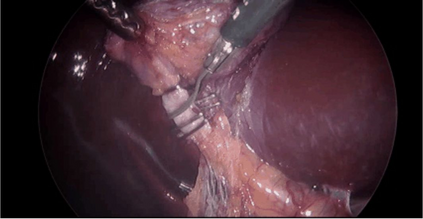

Large Vision-Language Models offer a new paradigm for AI-driven image understanding, enabling models to perform tasks without task-specific training. This flexibility holds particular promise across medicine, where expert-annotated data is scarce. Yet, VLMs' practical utility in intervention-focused domains--especially surgery, where decision-making is subjective and clinical scenarios are variable--remains uncertain. Here, we present a comprehensive analysis of 11 state-of-the-art VLMs across 17 key visual understanding tasks in surgical AI--from anatomy recognition to skill assessment--using 13 datasets spanning laparoscopic, robotic, and open procedures. In our experiments, VLMs demonstrate promising generalizability, at times outperforming supervised models when deployed outside their training setting. In-context learning, incorporating examples during testing, boosted performance up to three-fold, suggesting adaptability as a key strength. Still, tasks requiring spatial or temporal reasoning remained difficult. Beyond surgery, our findings offer insights into VLMs' potential for tackling complex and dynamic scenarios in clinical and broader real-world applications.